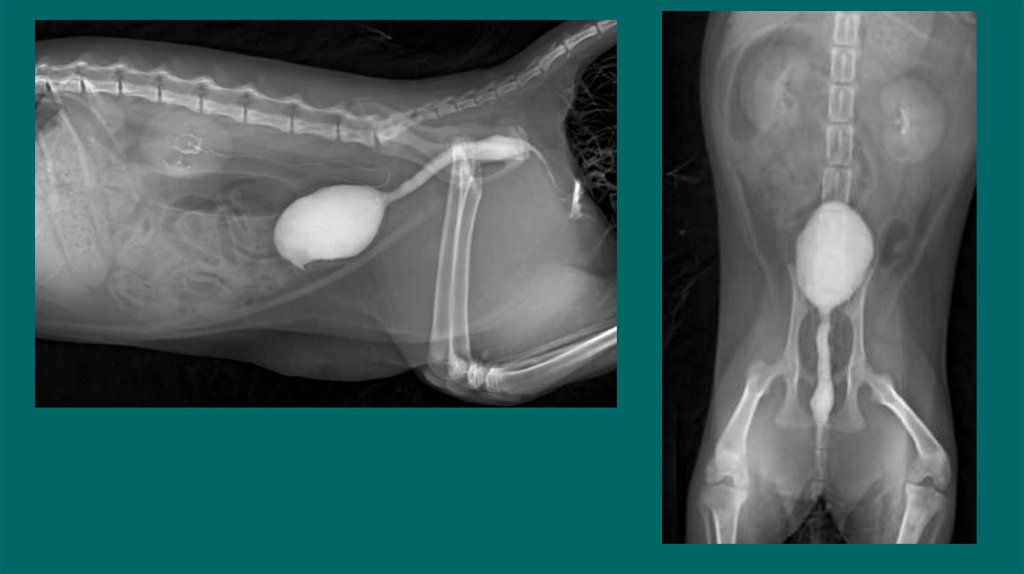

13. Позитивно-контрастная цистоуретрограмма

Показания:

Определение размера, формы и расположения мочевого пузыря

Определение проходимости или разрыва мочевого пузыря или уретры.

Обнаружение дефектов наполнения, связанных с уролитами (цистины/ураты) или гематомами,

выявления полипов или новообразований.

ПОДГОТОВКА

• Установка стерильного мочевого катетера для введения контраста

• Получение обзорных боковых и ВД снимков

• Введение стерильного йодсодержащего контраста в расчете 10мл/кг( разбавлен стерильным

физ.раствором 1:2 или 1:5)

• Выполняем латеральные/ВД снимки немедленно после введения контраста .

• Для получения уретрограммы оттянуть дистально катетер, ввести контраст одновременно сделать

боковой снимок ,провести серию снимков.

• Удаление контраста из мочевого пузыря по завершению